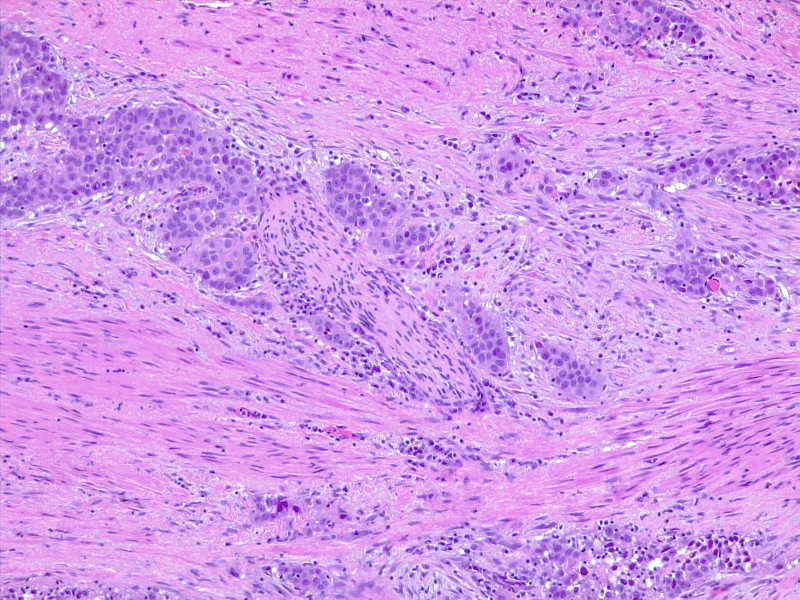

Urothelial carcinoma in situ in the setting of cystitis cystica et glandularis

圖2:膀胱炎和腺體的原位尿路上皮癌。由維基媒體 CoRus13 提供(公共領(lǐng)域 https://creativecommons.org/publicdomain/zero/1.0/deed.en)

Poorly differentiated urothelial carcinoma, with metaplastic squamous appearance

圖3: 分化差的尿路上皮癌,具有化生性鱗狀外觀。10x,H/E。醫(yī)學(xué)博士 Fabiola Farci 供稿